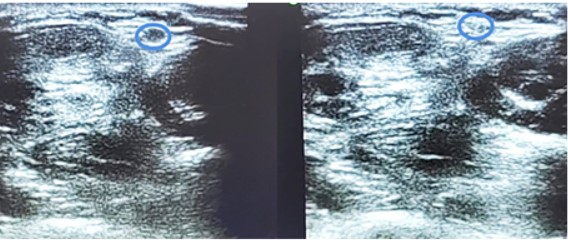

Las agujas se introdujeron inmediatamente adyacentes al nervio sural y su vena satélite por su lado medial. Se progresó con la introducción de las agujas a través de las fibras del tendón de Aquiles (Figura 6).

Figura 6. Ecografía corte transversal al tendón: En azul se identifica la vena safena menor. La línea punteada roja representa la posición del reparo (aguja 50.8 en contacto con el tendón de Aquiles).